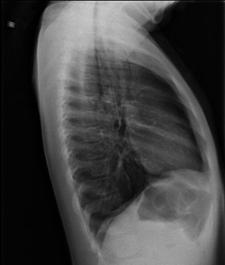

TRAUMATISME TORACICE

Fracturi costale multiple Hemitorace drept strivit

Volet costal si hemotorace

drept Fracturi costale multiple

Volet costal si hemotorace drept

Hemitorace drept strivit Hemitorace drept strivit Hemitorace drept strivit